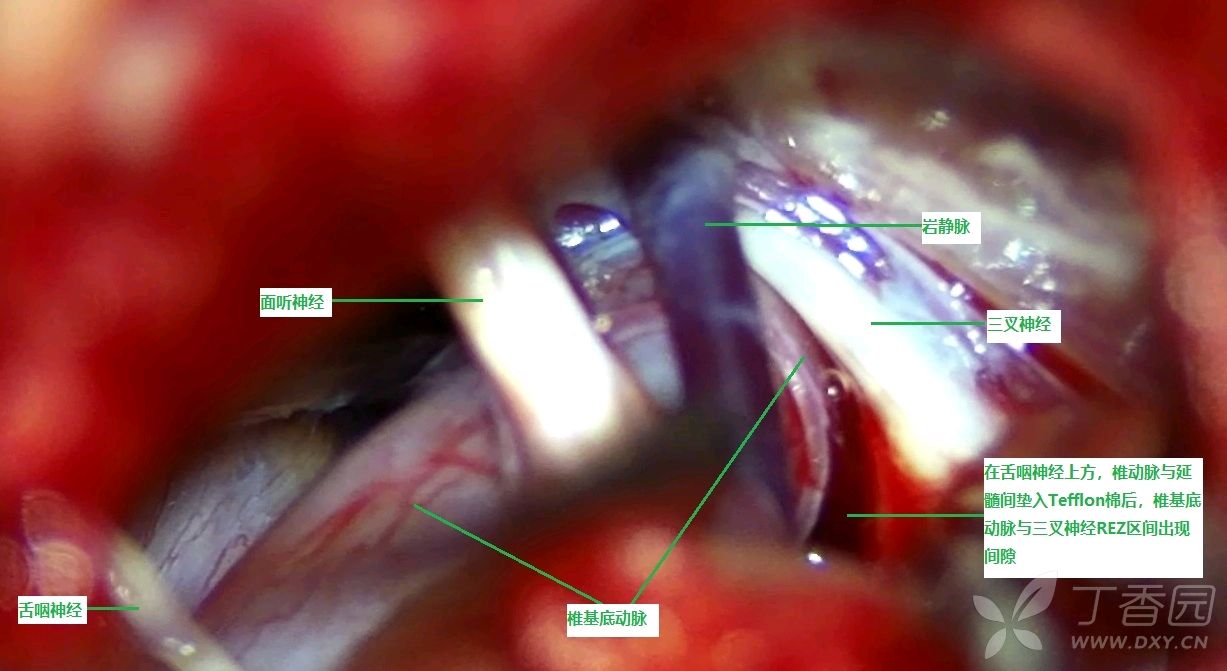

推移困难,如勉强垫入Tefflon棉,无法达到减压目的,术者选择于后组颅神经处(舌咽神经)沿三叉神经方向梳理椎基底动脉并垫入Tefflon棉(见图9)

图9 从舌咽神经处沿三叉神经方向梳理椎基底动脉并垫入Tefflon棉

见椎基底动与三叉神经REZ区及近段间出现腔隙,椎基底动脉张力明显降低(见图10)

图10 椎基底动与三叉神经REZ区及近段间出现腔隙